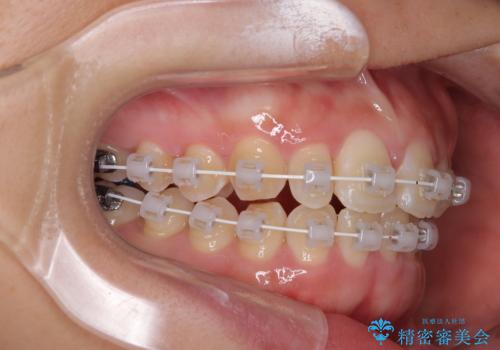

- 矯正装置

- 審美装置

- 治療計画

- 前歯のデコボコが気になるでのことで来院された患者様です。

歯列アーチが狭くスペース不足により前歯がデコボコしている状態でした。見た目を改善しつつ、前歯を前方に突出させず、自然な笑顔を目指したいというご希望でした。

治療計画

・アーチを側方に拡大して歯が並ぶスペースを確保

・抜歯は避け、非抜歯での対応

・目立ちにくい審美装置による矯正

・治療期間をできるだけ短縮するために、綿密な装置管理と協力体制を構築